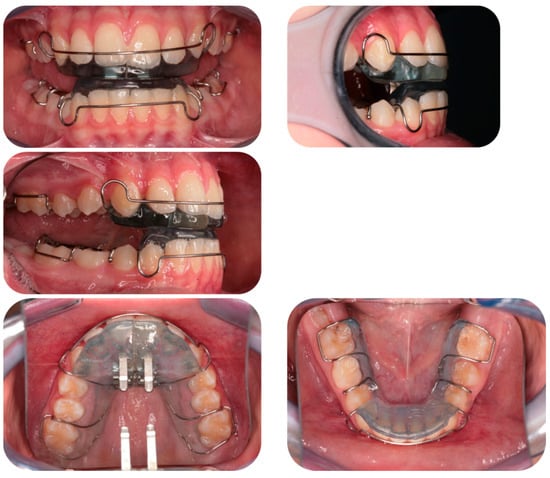

2.3. Sander Bite Jumping Appliance

The Sander Bite Jumping Appliance consists of two resin plates. The upper plate has a median expansion screw and two stainless steel extensions (prongs) that form a 60° angle with the occlusal plane. The lower plate has an inclined plane parallel to the prongs. Both plates have two Adam’s clasps for the first molars and a vestibular anterior arch which reaches the canines. The lower plate also has an incisal resin coating, which aims at reducing the vestibularization of the lower anterior teeth (Figure 3) [6].

Figure 3. Sander Bite Jumping Appliance.